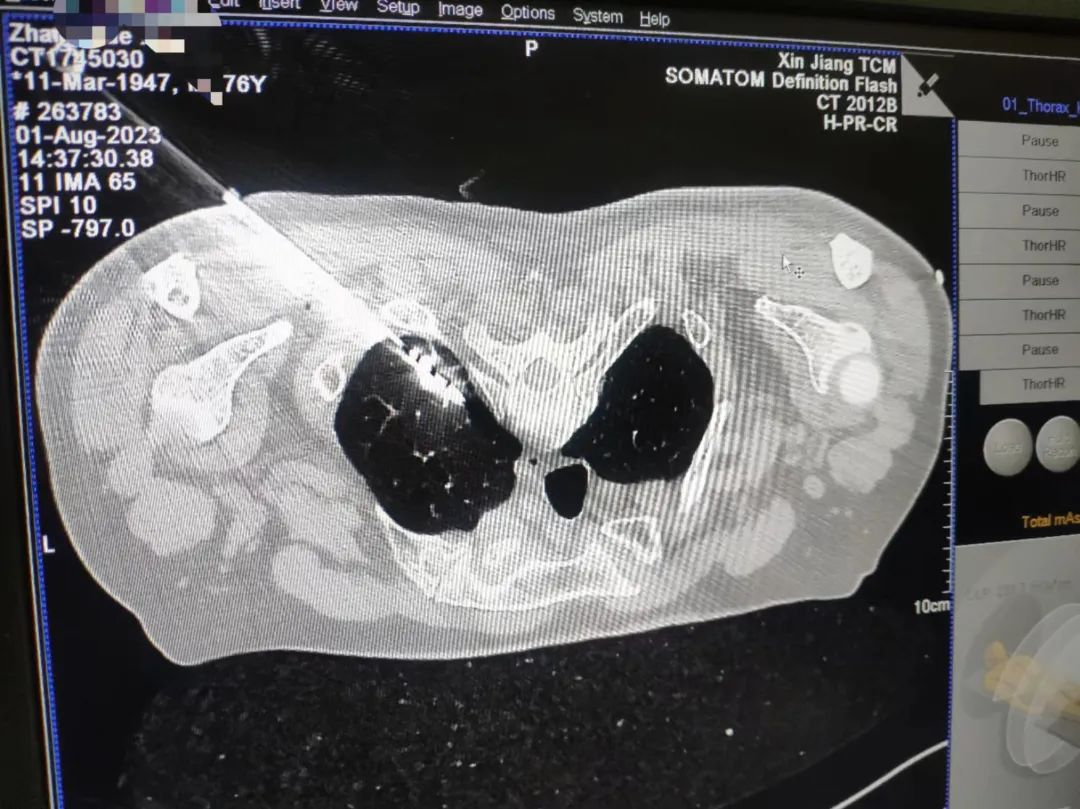

丁先生今年76岁,12年前曾经因结肠癌实施了手术,最近因身体疲劳来医院检查,发现左肺上叶2*2㎝不规则结节,呼吸一科为丁先生做了经皮肺结节活检术,术后病理诊断肺腺癌,考虑到既往患者有结肠癌手术史及慢阻肺病史,医生与丁先生及家人充分沟通后,决定行经皮穿刺肺部肿瘤微波消融术,术后患者未出现气胸及胸腔出血等并发症。

术中表现如下:消融贯穿结节产生电磁流进行震荡,对局部组织加热,造成肿瘤的热凝固坏死